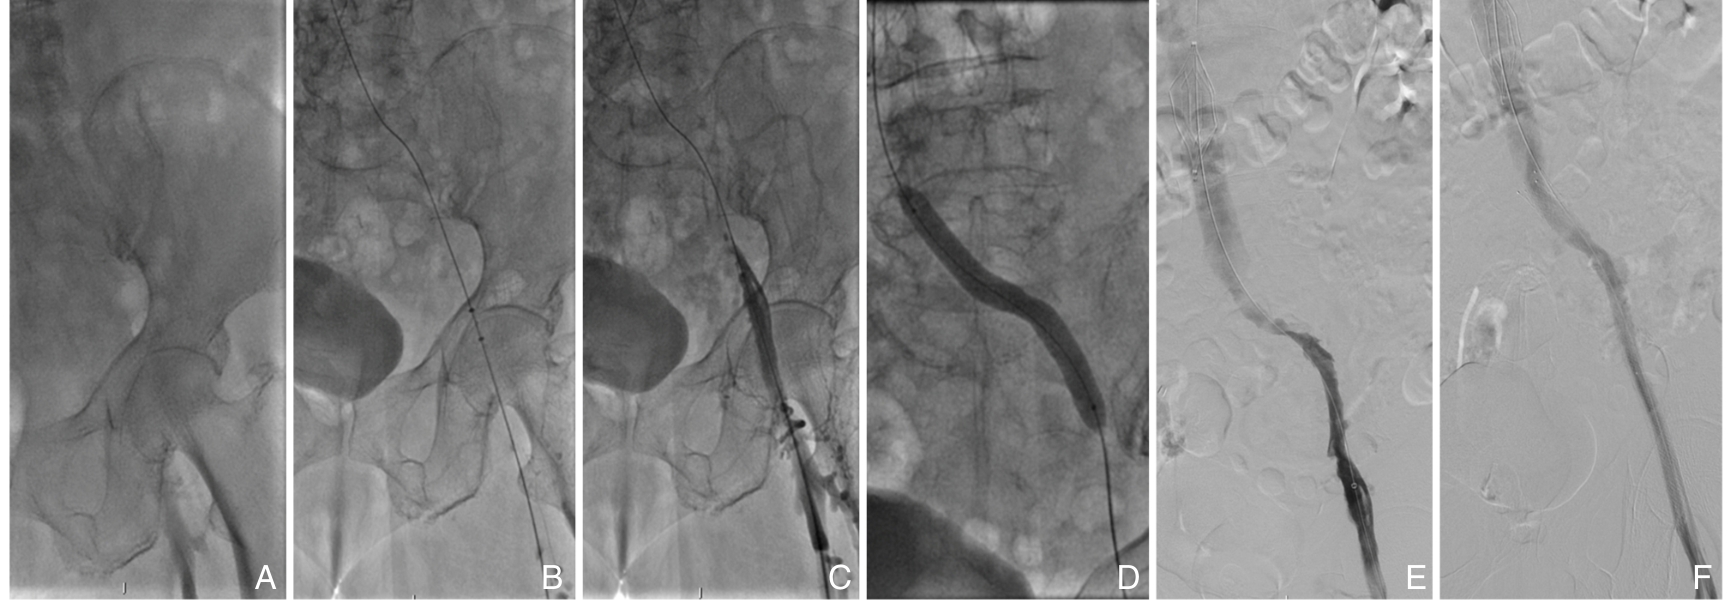

2025, 34(12):2619-2626. doi: 10.7659/j.issn.1005-6947.250158

摘要:背景与目的 急性门静脉血栓形成可导致肠坏死、消化道大出血等严重并发症,单纯抗凝治疗的血栓再通率有限。本文总结经腹小切口直视下穿刺肠系膜上静脉,联合AngioJet溶栓吸栓及球囊扩张治疗急性门静脉血栓形成的临床效果与安全性。方法 回顾性分析2023年7月—2024年12月北京大学人民医院收治的10例急性肠系膜上静脉-门静脉血栓形成患者。所有患者均在全麻下经腹正中小切口直视穿刺肠系膜上静脉,应用AngioJet机械溶栓吸栓联合球囊扩张成形治疗。记录术中即刻血栓清除率、围术期并发症及随访期门静脉系统再通情况。结果 10例患者手术时间中位数为140(110~245)min,不含AngioJet系统相关出血的中位术中出血量为80(50~200)mL;AngioJet机械血栓抽吸系统血栓抽吸时间173(138~296)s。术后即刻血栓清除率Ⅲ级7例,Ⅱ级3例,手术技术成功率为100%。围术期并发症包括腹腔出血1例、切口血肿1例,均经处理后好转。所有患者术后腹痛症状明显缓解,无肠坏死、肠梗阻及急性肾功能不全发生。中位随访时间5个月,门静脉系统完全再通5例,部分再通4例,血栓稳定1例,无血栓新发或复发,随访期内无抗凝相关出血及死亡。结论 经腹直视下穿刺肠系膜上静脉,联合AngioJet溶栓吸栓及球囊扩张治疗广泛急性门静脉-肠系膜上静脉血栓形成安全、有效,可迅速恢复门静脉系统血流,缓解症状并避免肠坏死。